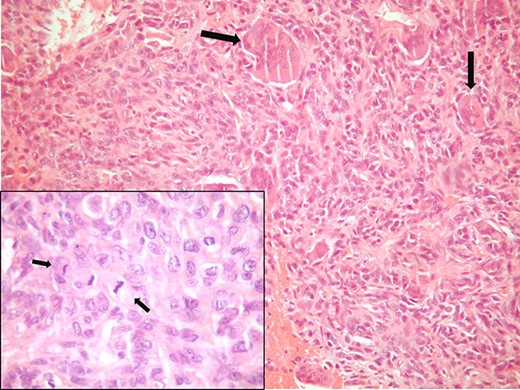

A 62-year-old Caucasian male was referred from a private practice to the emergency department of our hospital, because of persistent macroscopic hematuria and hydronephrosis of the left kidney, due to a sizeable tumor of the urinary bladder. He was a smoker (~40 pack years), had no relative family history and no other comorbidities. Initial imaging with abdomen ultrasound showed an intraluminal bladder tumor (91×59mm) and a third-grade dilatation of the left pelvicalyceal system. Under antibiotic prophylaxis, transurethral resection (TUR) successfully controlled the hematuria. Moreover, a nephrostomy tube was placed on the left kidney. The histologic report documented a muscle-invasive (pT2) high-grade carcinoma with features of osteoclast-rich UC. After the TUR, detailed imaging (abdomen and thorax computed tomography, bone scintigraphy) showed cT3N0M0 disease. On this basis, a radical cystoprostatectomy and pelvic lymphadenectomy with a Bricker ileal conduit urinary diversion (RCPL-BUD) was performed. Histological examination revealed a pT4aN2M0 tumor with a biphasic appearance, with a mixture of mononuclear malignant epithelial cells and multinucleated osteoclast-like reactive giant cells. Mononuclear cells had abundant cytoplasm, round to oval vesicular nuclei and mild to moderate atypia. Mitotic figures were frequent (shown in Fig. 1). No finding of high-grade papillary or in situ UC was detected. Immunohistochemical examination revealed that the mononuclear malignant epithelial cells were positive for cytokeratins AE1/AE3, p63 and GATTA-3. The giant cells were positive for CD 68 (shown in Fig. 2). Subsequently, the patient was referred to the Oncology Department of our hospital for adjuvant cisplatin-based chemotherapy. The patient experienced recurrence and progression at about 7 and 11 months, respectively, after the RCPL-BUD. He died about 13 months after the original TUR diagnosis. This research complies with the guidelines for human studies and was conducted ethically in accordance with the World Medical Association Declaration of Helsinki.

Pathologic examination shows osteoclast-like giant cell carcinoma (H&E, ×100). Insert (H&E, ×400).

ORUC of the UT closely recapitulates the morphology of osteoclastic GCTB or soft tissues. Histopathologically, the tumor has a biphasic appearance with a mixture of mononuclear malignant epithelial cells and multinucleated osteoclast-like reactive giant cells. Mononuclear cells have abundant cytoplasm, round to oval vesicular nuclei, mild to moderate atypia and variable mitotic activity. Severe pleomorphism is not usually seen. Mitotic figures are often frequent and atypical mitoses can be observed. The giant cells are morphologically and immunohistochemically identical to osteoclasts and are regarded as being of histiocytic origin. They are cytologically bland, may exhibit phagocytic activity but no mitotic activity and are uniformly distributed among mononuclear cells although they may condense around hemorrhagic foci. Prominent vascularity, large areas of hemorrhage, blood-filled cysts, red extravasation and deposition of hemosiderin, multinodular or sheet-like growth pattern and phagocytosis by giant cells are also common features with GCTB. In most cases, there is an associated high-grade papillary or in situ UC. Immunohistochemically, mononuclear cells are positive for cytokeratin, EMA, vimentin, Ki67, p53, GATA 3, thrombomodulin and p63 [5]. Giant cells are positive for CD68, alpha-1 antitrypsin, acid phosphatase, vimentin, CD51, CD54 and negative for cytokeratin, EMA, GATA 3, thrombomodulin, Ki67 and p53 [5]. The rarity of this neoplasm and its resemblance to other giant-cell rich processes may pose diagnostic difficulties. The differential diagnosis mainly includes pleomorphic giant cell carcinoma, foreign-body type giant cell reaction and the giant cell carcinoma that shows obvious malignant bizarre giant cells.